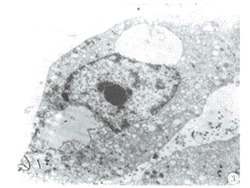

图3透射电镜观察100μmol/L人参皂甙Rg1处理72h,培养细胞的超微结构(×5000)

(一)人参总甙、人参皂甙Rg1诱导体外培养B16F10细胞形态学改变:用50μg/mL人参总甙、100μmol/L人参皂甙Rg1处理细胞,24h即发现部分培养细胞变圆,树状突消失、脱壁以及不规则球形体产生(图1)。这种变化以100μmol/L人参皂甙Rg1作用48~72h最为明显。经AO/EB双重荧光染色发现这些细胞体积变小,核着色呈黄绿色,荧光强度增强(图2),判断为早期凋亡细胞形态改变[4]。用透射电镜技术观察经人参皂甙Rg1处理细胞的超微结构时,发现细胞呈现核异染色质边集、核空泡化、染色体固缩等变化,细胞内能见到Ⅲ~Ⅳ期黑素小体(图3),符合凋亡细胞形态学改变。